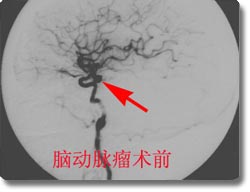

开展了脑动脉瘤、脑血管畸形、颈内动脉海绵窦瘘、脊髓血管畸形的神经介入治疗和恶性肿瘤的次选择性化疗,尤其是对巨大动脉瘤的栓塞成功率达到国内领先水平。同时开展了脑动脉瘤、动静脉畸形、高血压脑出血的手术治疗和血管闭塞性疾病的颅内外搭桥手术、颈内动脉内膜切除术、急性栓塞的溶栓治疗术、血管内支架放置手术,颅内动脉瘤电解可脱性螺旋圈(CDC)治疗,先后收治病人4000余例,积累了丰富的经验,为脑血管狭窄、脑供血不足及脑血栓病人的康复提供了有力保证。介入治疗具有不出血、无感染、损伤小、风险小、恢复快的优点,是脑血管疾病病人的理想选择。2003年,与北京宣武医院强强联合成立了北京市脑血管病中心重庆分中心。2005年成功地承办了第七届全国神经外科血管内治疗研讨会,受到了与会专家的一致赞誉。